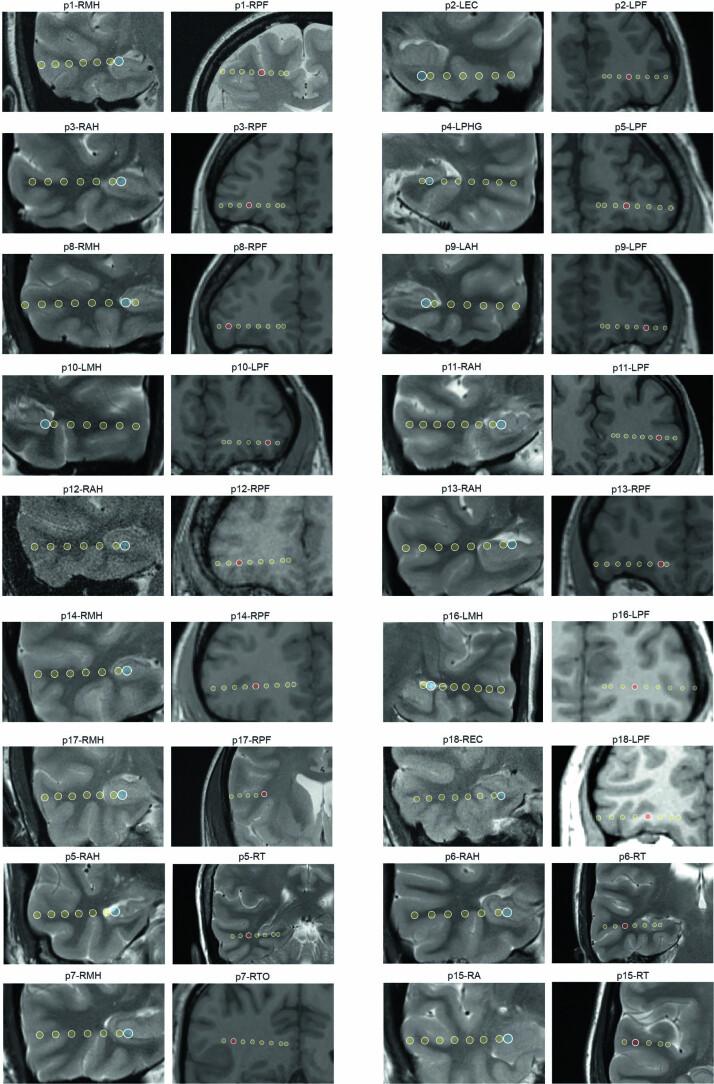

https://cdn.ncbi.nlm.nih.gov/pmc/blobs/faf5/10244181/fd6cc457ef3c/41593_2023_1324_Fig14_ESM.jpg